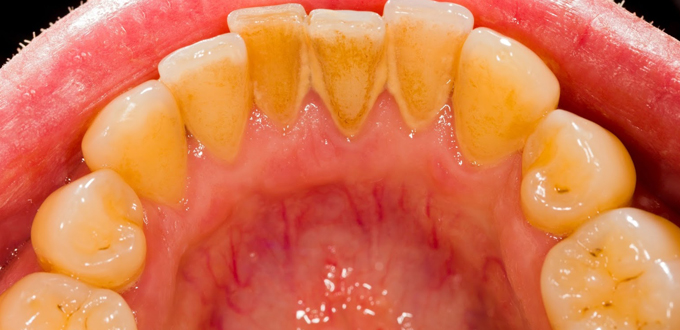

Cara Menghilangkan Plak Di Gigi

Cara Mudah Membersihkan Karang Gigi Tanpa Harus Ke Dokter

7 Cara Menghilangkan Karang Gigi Dengan Bahan Alami Ampuh Dan

Cara Menghilangkan Karang Gigi Yang Membandel